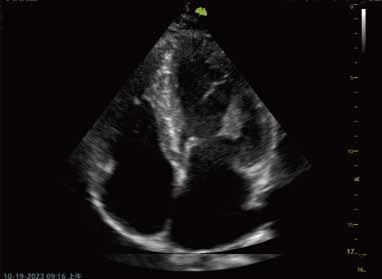

Apikale 4-Kammer